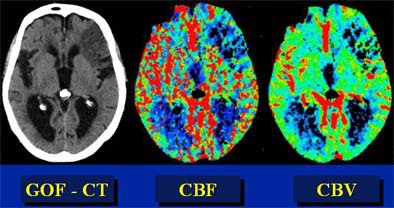

In recent years, researchers have performed CT studies that demonstrate the same information. Initial-phase CT will show ischemic penumbra as a region of normal or increased cerebral blood volume (> 2.5 ml per 100 g of brain tissue) in the region, combined with a decrease in CBF of more than 34%, he said. Once the tissue dies, CBV will also decrease.

"So decreased CBV is dead brain, whereas normal or increased CBV in the setting of decreased CBF is penumbra," he explained. Parametric color maps based on CBV, CBF, and mean transit time (MTT) can be used to illustrate the penumbra.

| In this patient, "good old-fashioned" (GOF) head CT (left) depicts acute infarction in the left frontal lobe. Perfusion imaging was performed to assess the presence of penumbra. However, parametric color mapping shows substantially matched CBF and CBV, indicating infarcted tissue that is not salvageable. Images courtesy of Dr. Jay Cinnamon. |